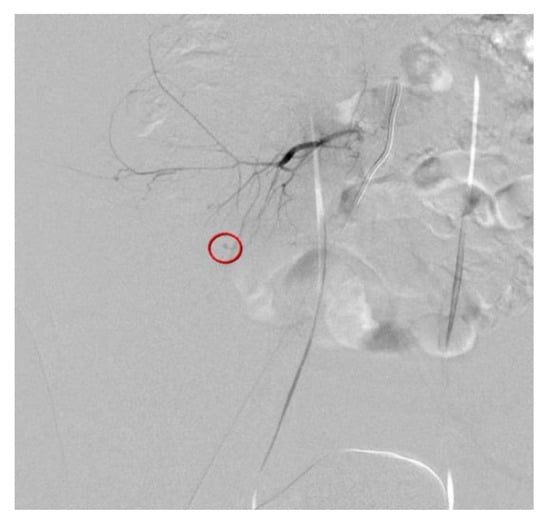

Figure 3. Transcatheter arterial embolization (TAE) of the ruptured fifth lumbar artery was successfully performed using Gelfoam particles (Figure 3). The patient recovered uneventfully and was discharged 4 days after TAE, without any complications or blood transfusion. After 1 month of follow-up, the patient recovered uneventfully, and no hemorrhage-related complications were observed. Iatrogenic lumbar artery injury during PDN is rare, but may be a serious condition that requires early detection and urgent treatment. Great care should be taken to avoid hemorrhagic complications, and adequate an technique and anatomical considerations are important to avoid these complications. Transarterial embolization, rather than open hematoma evacuation or laparotomy, can be a safe and effective treatment to stop active bleeding. Successful embolization of the bleeding vessel is performed using Gelfoam particles (circle).